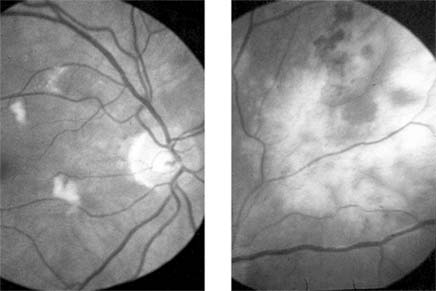

Ocular tuberculosis results from endogenous spread from systemic foci. The incidence of eye involvement is less than 1% in known cases of pulmonary tuberculosis; granulomatous panuveitis and retinal "cold" abscesses may occur (Figure 15-24). There has been a recent increase in the incidence of tuberculosis as a result of the spread of AIDS infection.

Figure 15-24

Figure 15-24: Tuberculosis. Cold abscess. A young man presented with a swelling on his back (left) and a choroidal lesion (right). Aspiration of the abscess revealed Mycobacterium tuberculosis.